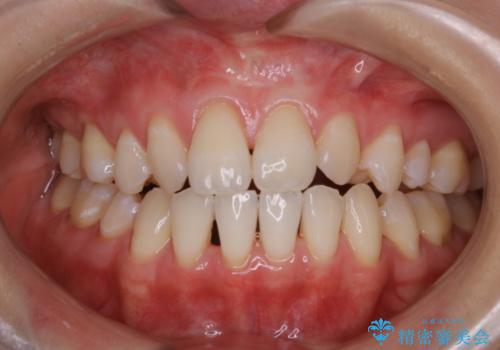

office-whitening(エクセレント)

治療症例の内容

- 20代女性

- 1日

- 1回

- なるべく1回で白くしたいとのことで来院されました。効果をより高めるために処置前クリーニング(¥3300)を行ってから、オフィスホワイトニングのエクセレントコース(¥29700)を行いました。

- ¥33000費用は治療当時の料金となります